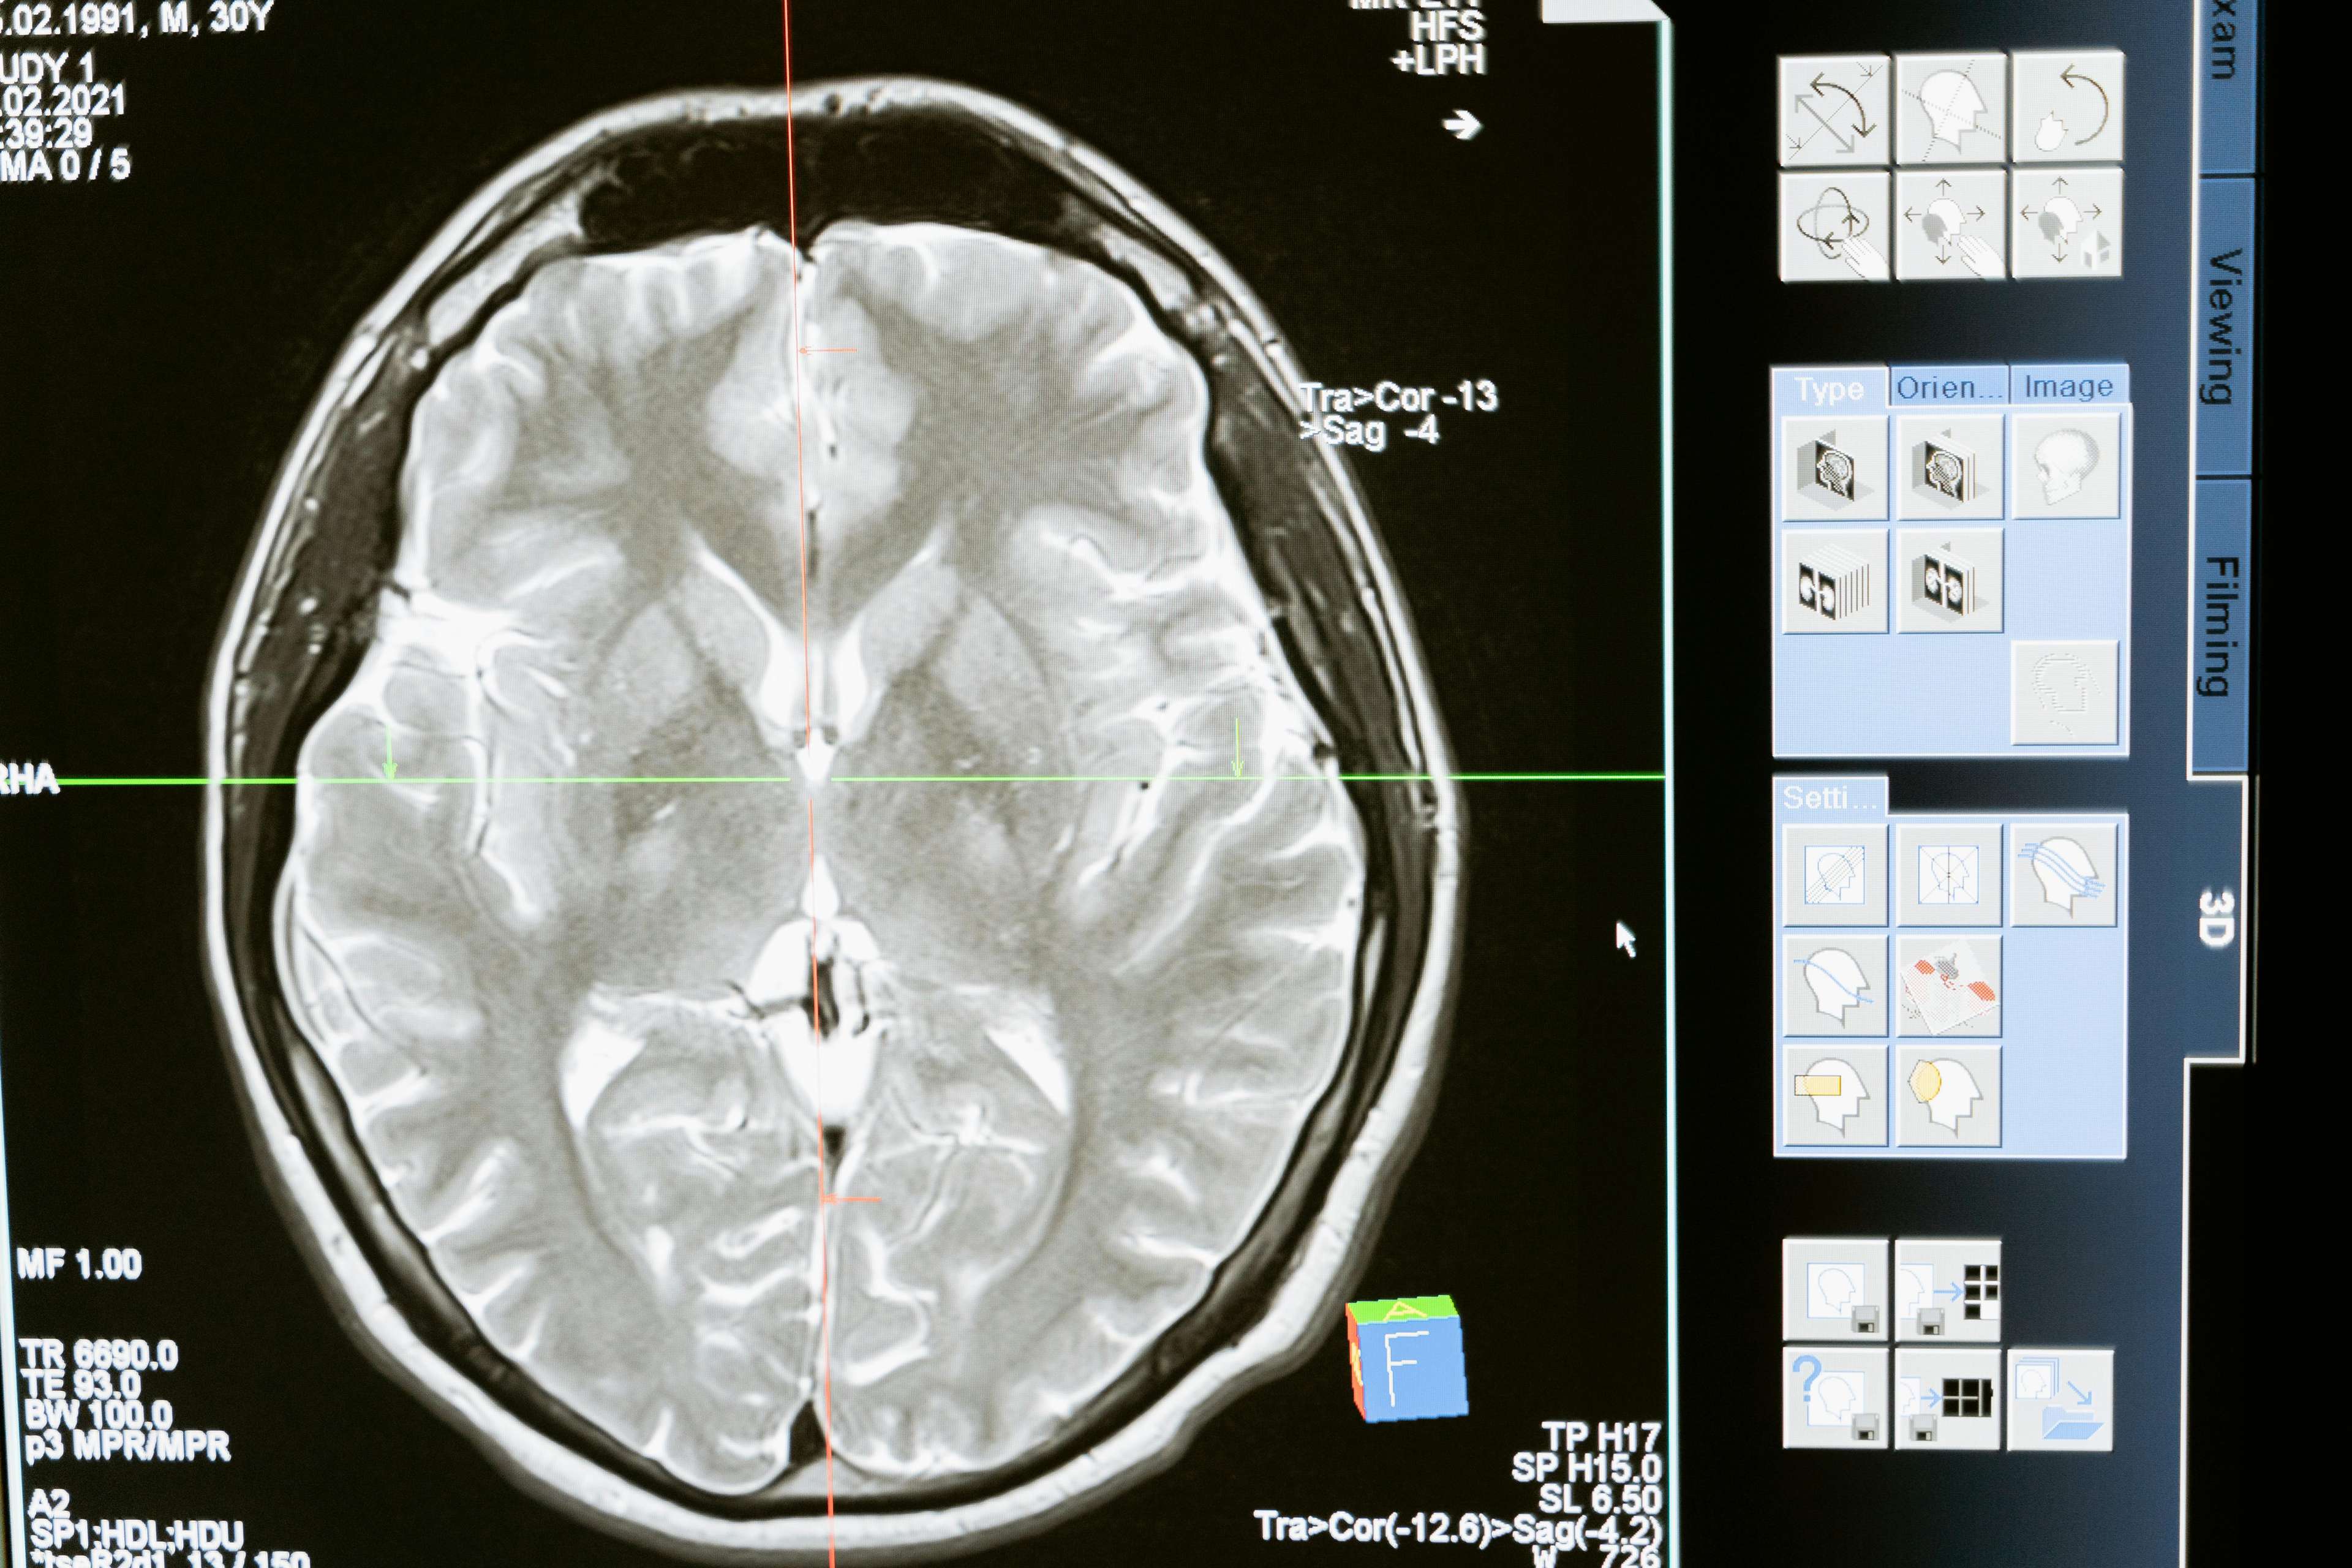

DBS is a surgical procedure that involves implanting a device that sends electrical impulses to specific areas of the brain, effectively "rewiring" the neural connections responsible for symptoms of various neurological disorders. This innovative treatment has been instrumental in alleviating the suffering of individuals with conditions such as Parkinson's disease, dystonia, obsessive-compulsive disorder (OCD), and epilepsy, among others. By targeting the root cause of these conditions, DBS has been shown to significantly improve motor function, reduce tremors, and enhance overall quality of life.

Unlocking the Secrets of the Brain

So, how does DBS work its magic? The answer lies in the intricate complexities of the human brain. You see, our brains are wired with an intricate network of neurons that communicate with each other through electrical impulses. In individuals with neurological disorders, these impulses can become disrupted, leading to a breakdown in communication and, ultimately, the manifestation of symptoms. DBS works by implanting a device that sends electrical impulses to specific areas of the brain, effectively "resetting" the neural connections and restoring balance to the brain's delicate ecosystem.